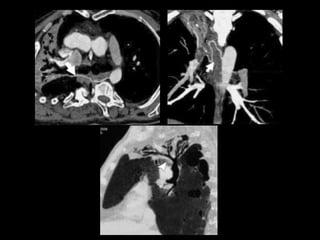

AngioTC Hemoptisis

• Diagnosticar causa del sangrado y obtener

mapa vascular angiográfico para embolización.

• Valorar patología pulmonar relacionada.

Protocolo AngioTC Torácico

• Desde base cuello hasta nivel de arterias renales

para incluir troncos supraaórticos y arterias

infradiafragmáticas.

• 0.8/1 mm. grosor de corte

• 100-120 ml contraste yodado no iónico a 4cc/sg.

• ROI en Aorta descendente.

• Reconstrucciones multiplanares y volumétricas

(MIP y VR): coronales (arterias mamarias internas

e intercostales) y axiales (arterias frénicas

inferiores y tronco celiaco).

AngioTC Hemoptisis • Diagnosticarcausa del sangrado y obtener mapa vascular angiográfico para embolización. • Valorar patología pulmonar relacionada. • Limitación: lesiones endobronquiales o intracavitarias ocultas por sangrado.

Protocolo AngioTC Torácico •Desde base cuello hasta nivel de arterias renales para incluir troncos supraaórticos y arterias infradiafragmáticas. • 0.8/1 mm. grosor de corte • 100-120 ml contraste yodado no iónico a 4cc/sg. • ROI en Aorta descendente. • Reconstrucciones multiplanares y volumétricas (MIP y VR): coronales (arterias mamarias internas e intercostales) y axiales (arterias frénicas inferiores y tronco celiaco).